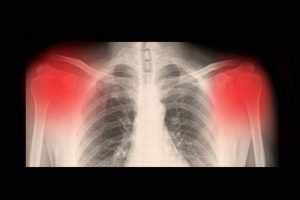

一般來說,診斷可以經由臨床試驗來完成,通常是透過X光、電腦斷層掃描和/或磁振造影檢查來完成的。此外,骨關節炎的程度可以經由高解析度超音波來檢測。